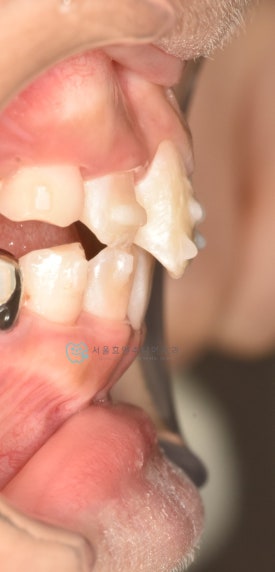

치료 후 - 유치 어금니들이 빠지고 영구치가 맹출하고 있습니다.송곳니가 나올 공간을 충분히 마련하며 확장하여 고른치열을 완성했습니다.

이대로 끝내도 좋겠지만 어린이투명교정치료의 18개월 기간이 아직 만료되지 않았습니다. 영구치 어금니 맹출을 조금 더 기다리다가 송곳니 어금니들이 맹출되면 그때 다시한번 장치를 만들어 앞니 디테일 마무리와 함께 새로 맹출하는 이들을 완벽하게 하고 마무리해하면 2차교정이 필요없을 것으로 생각됩니다.

자세히 보면 아래 영구치 어금니의 충치도 치료하는 과정에서 깨끗하게 레진치료 해주었습니다. 교정하면서 충치검진이나 치료를 위해 다른 치과에 내원하지 않아도 된다는 점이 바쁜 우리 아이들에게는 큰 장점으로 다가오는 것 같습니다. 서울효앤주니어치과에서 교정체크 = 충치검진